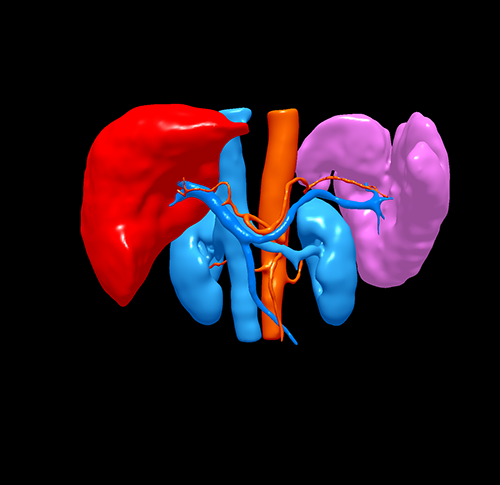

S7肝癌 门脉高压脾亢---S7切除 贲门周围血管离断